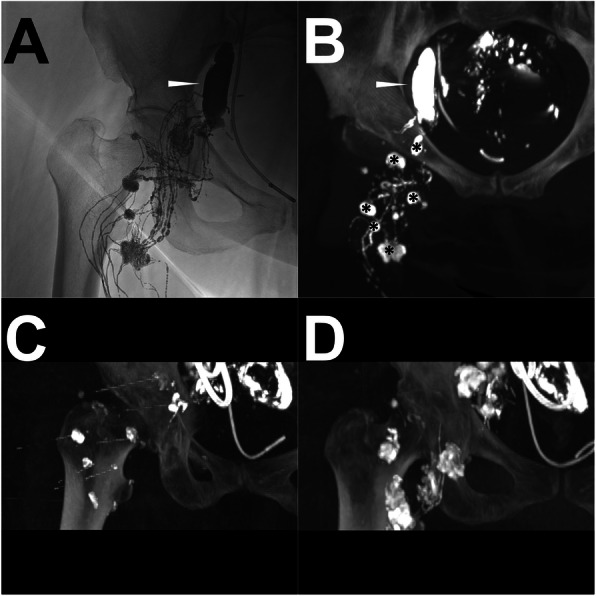

Fig. 5.

A patient underwent a DLS procedure after post-LAG CT. Note: Conventional iodized oil-based LAG showed the extravasation (black arrowhead) from the left iliac LVs (a). From the sagittal (b) and axial MIP (c) images of post-LAG CT is demonstrated an obvious LF (white arrowhead) from the iliac LVs into the peripheral lymphocele around the transplanted kidney. The afferent LNs could be identified (*). A pigtail drainage catheter was inserted into the lymphocele before the local sclerotherapy (d). After running out of all the lymphatic fluid, 15 ml of 95% Ethanol as the sclerosant was injected to flush the lymphocele and then this was drawn out twice. Eight (8) days after DLS, the CT scan revealed very limited residual lymphatic fluid (e, f). Abbreviations: DLS – direct leakage sclerotherapy; post-LAG CT – post-lymphangiographic computed tomography; LAG – lymphangiography; LVs – lymphatic vessels; MIP – maximum intensity projection; LF – lymphatic fistula; LNs – lymph nodes